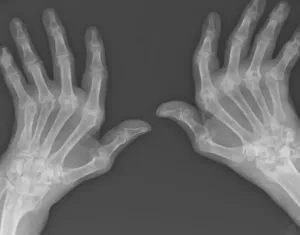

Can Chiropractic Help My Rheumatoid Arthritis Hands?

The RA co-management may be with rheumatoid drugs. Still, many decide to use a monitored...